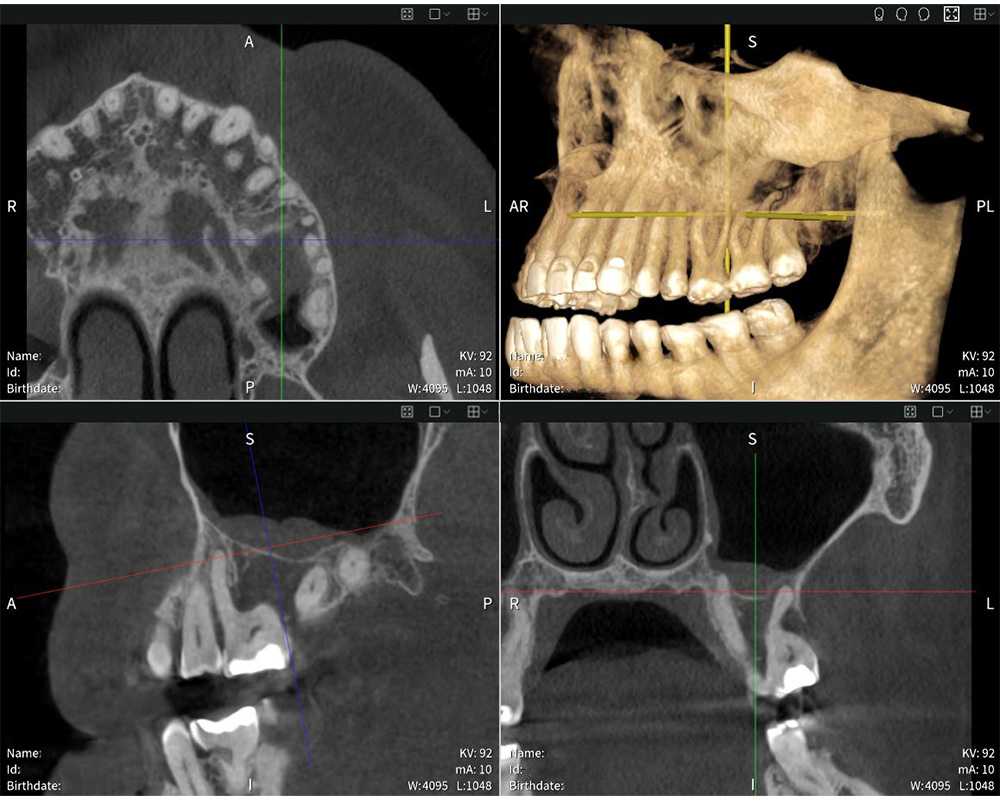

Seethrough Max puts usability first. Its open design and generous dimensions ensure maximum patient comfort and tolerance, while face-to-face positioning simplifies interaction between user and patient. “The positioning process is excellent. I appreciate being able to face the patient directly and maintain eye contact, which helps me guide them into the optimal position for a precise scan”, says Dr med. dent. Mauro Amato. Complementing the hardware, Seethrough Studio ensures sharp, detailed, and undistorted images. Its advanced patient motion correction algorithm enhances image quality in both 3D and 2D imaging. Offering a field of view of up to 17 × 17 cm, Seethrough Max covers a wide variety of applications, from endodontics and implantology to oral surgery and ENT – all while keeping radiation exposure low. “The X-ray images are exceptionally sharp and detailed, enabling highly accurate diagnoses and precise treatment planning”, says Dr med. dent. Mauro Amato.